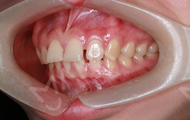

最后给大家展示一下口内的效果吧,如果我不说你能看到我戴了牙套吗?发音也还好,跟没戴牙套之前没有什么区别呢~

接下来去拍片的时候,还有护士姐姐给穿放射服,服务要不要这么周到~~来前我做好拔牙准备了,但医生给我制定的方案不需拔牙,因为收紧牙缝就好,还是小高兴了一会儿~拍了口内照、正面、侧面、45度的照片,OMG!设备简直不要太先进,医生讲解的很耐心,真的内心有点迫不及待了!!!